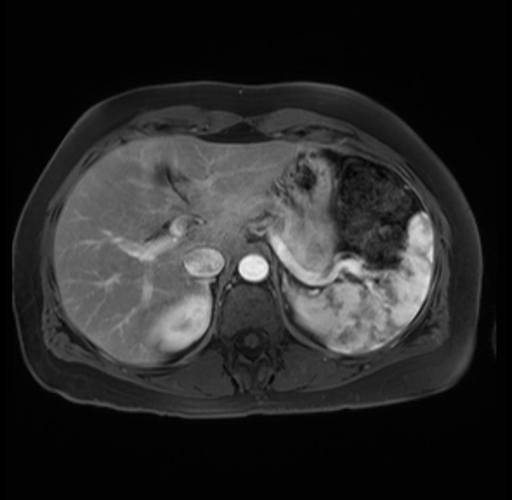

Imaging Analysis

Look through the patient's CT scan to identify any areas of concern for the necessary procedure.

Based on your CT findings, which issue(s) are present and would give reason for "planned slowing down moment(s)" in this case?

Considering a standard distal pancreatectomy procedure, what step(s) of the operation would you do differently in this case?